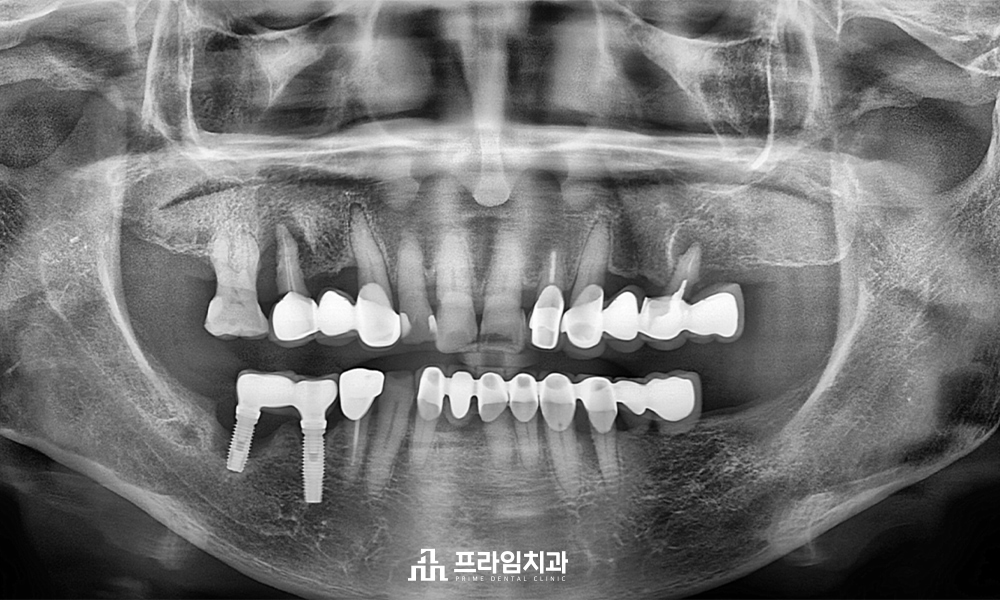

전체적인 파노라마 사진을

촬영해 보았을 때,

왼쪽은 이미 어금니 부위를 상실하여

브릿지 형태로 치료를 받아

힘을 받고 있는 치아들의

상태가 좋지 않음을 알 수 있었고

오른쪽은 기존 아래 임플란트 주위와

위쪽 자연 치아의 주위로 잇몸뼈가

많이 녹아 예후가 좋지 않음이 관찰되었습니다.

하여, 예후가 좋지 않은 치아들은

모두 발치한 후 임플란트 식립 계획을

수립하였습니다.